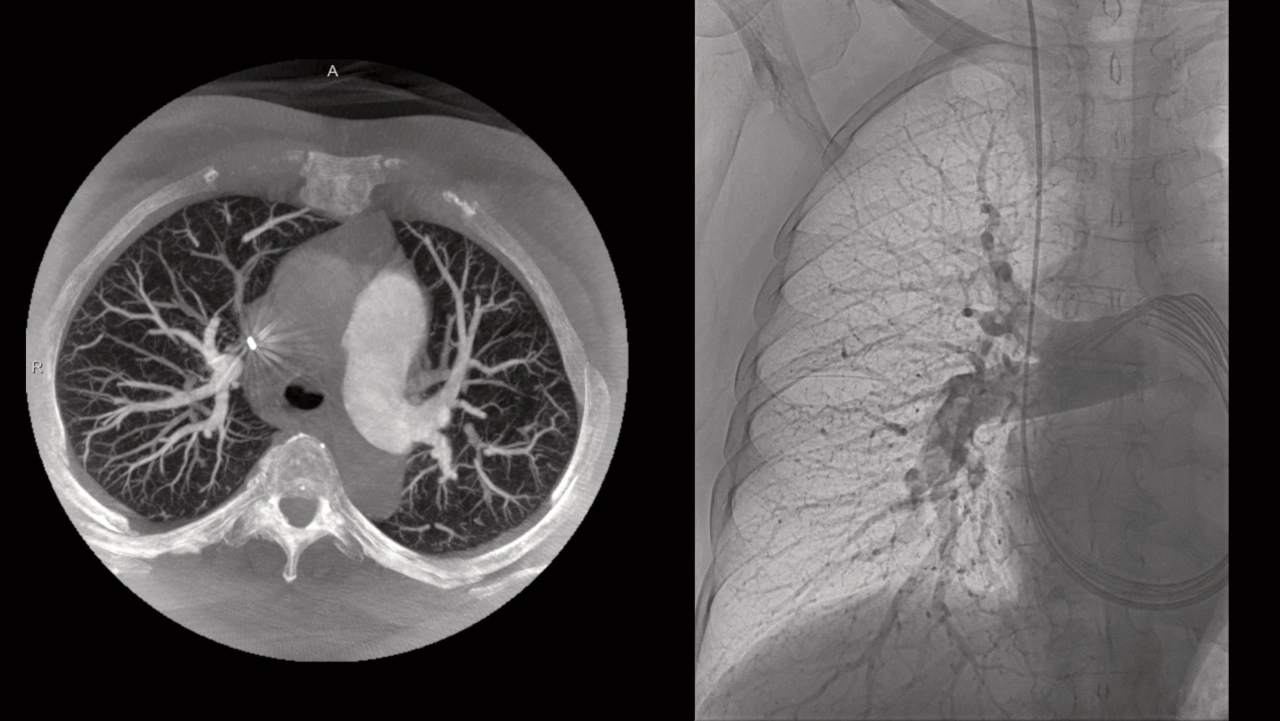

Für eine präzise Rekonstruktion erfasst Artis icono ceiling dreidimensionale Daten sowohl kopfseitig als auch von der Seite über den vollständigen Winkelbereich von 200 Grad hinweg. Dies ist besonders in der Interventionellen Radiologie von Bedeutung, da 3D-Schnittbildgebung von der Seite bei Tumor- und Prostata-Embolisationen eine wichtige Rolle spielt.

Um eine konstant hohe Bildqualität bei möglichst niedriger Dosis zu ermöglichen, hat Siemens Healthineers für die Artis-icono-Familie eine neue Bildkette namens Optiq entwickelt. Im Zusammenspiel von Hard- und Software sorgt diese Bildkette für optimierten Bildkontrast und reduziert Rauschen – unabhängig von der Physiognomie der zu behandelnden Person. Für eine präzise Rekonstruktion erfasst Artis icono ceiling

dreidimensionale Daten sowohl kopfseitig als auch von der Seite über den vollständigen

Winkelbereich von 200 Grad hinweg. Dies ist besonders in der Interventionellen Radiologie von Bedeutung, da 3D-Schnittbildgebung von der Seite bei Tumor- und Prostata-Embolisationen eine wichtige Rolle spielt.

Ballon-Angioplastie bei chronisch thromboembolischer pulmonaler Hypertonie. Mit freundlicher Genehmigung der Medizinischen Hochschule Hannover